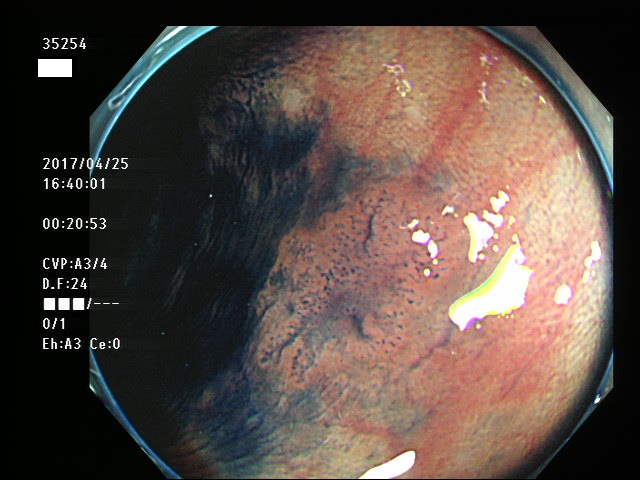

上記100名より抽出した平坦・陥凹型腺腫・SSAP(=癌化の危険が高いが見落としやすい病変)の内視鏡写真

35200 35201 35206 35207 35208 35209 35211 35213 35215 35217 35218 35219 35221 35223 35224 35225 35227 35231 35232 35233 35234 35235 35237 35238 35245 35249 35254 35255 35256 35257 35258 35264 35265 35266 35270 35271 35275 35276 35277 35280 35281 35283 35284 35285 35286 35287 35289 35290 35291 35292 35293 35294 35295 35298